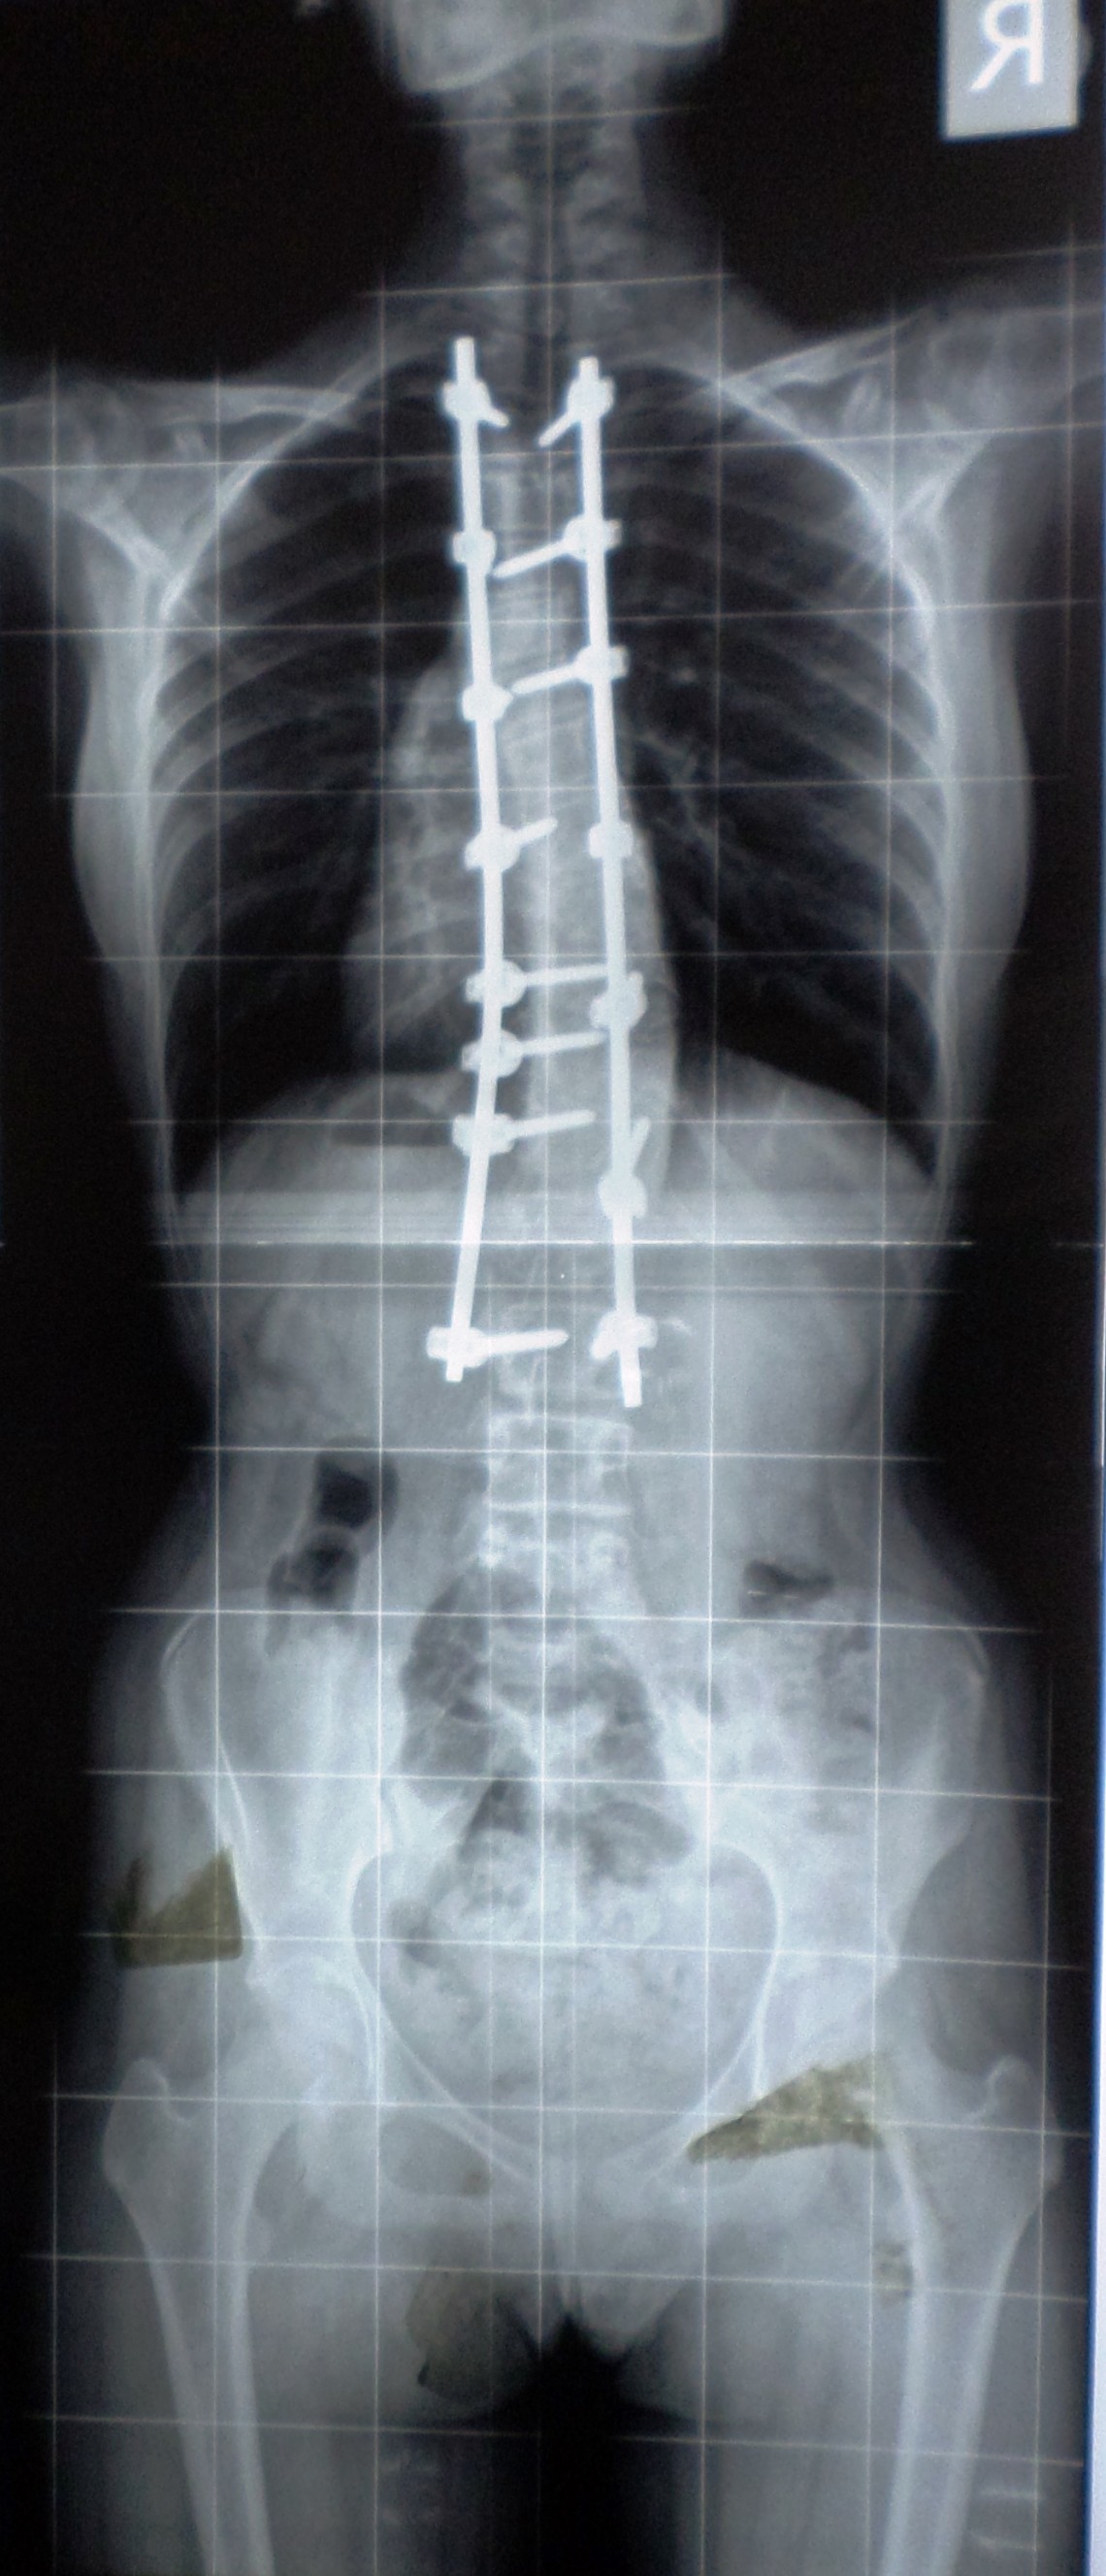

Farklı tipte skolyozu olan hastaların ameliyat öncesi ve sonrası fotoları: